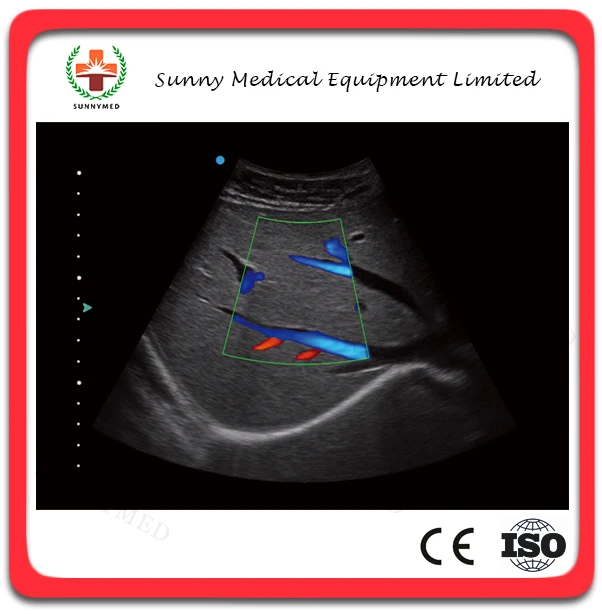

SY-A2300 Cardiac Diagnosis Portable Ultrasound Scanner, Excellent Image 3D 4D Echo Machine